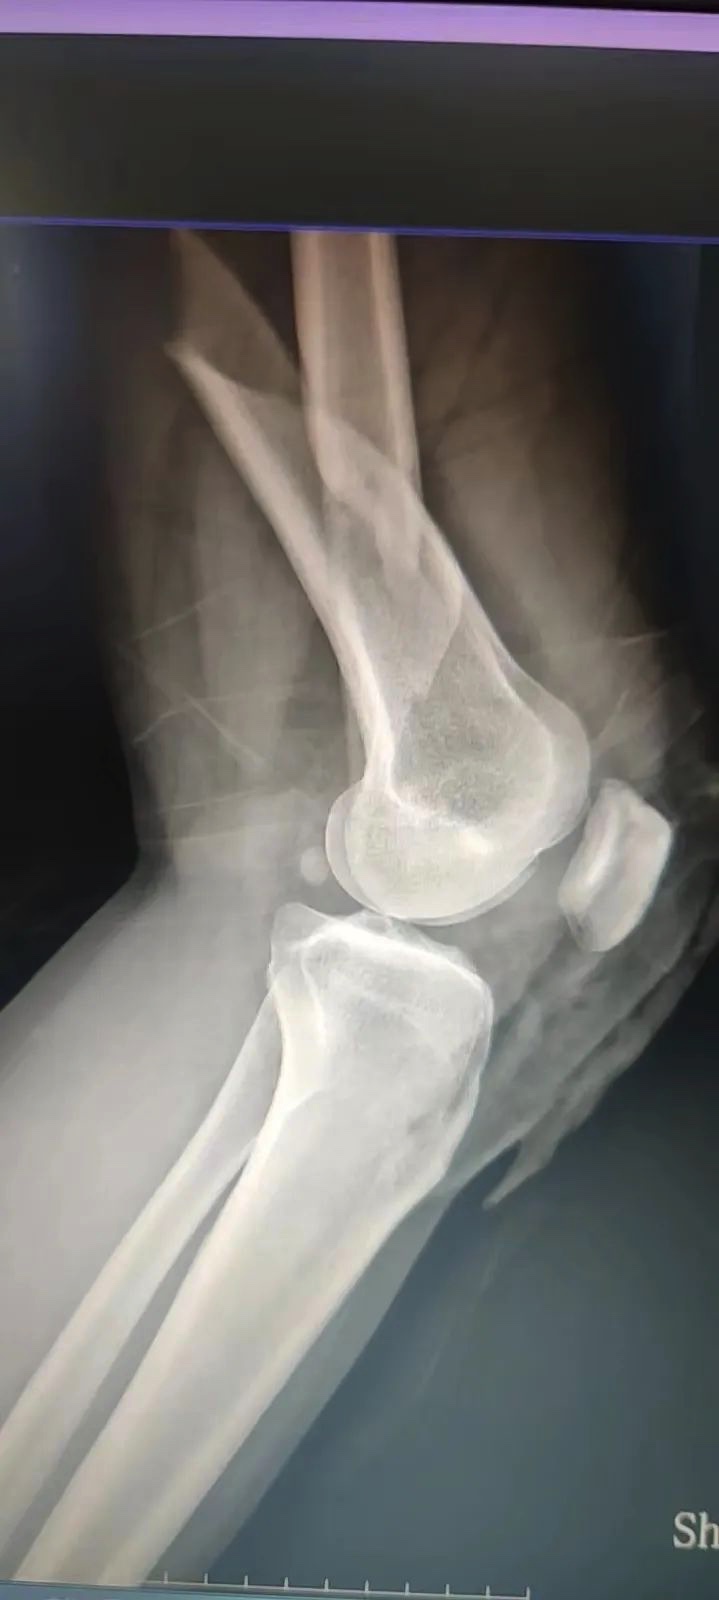

今天上午,在江桥医院住院部,医生在为刚做好手术的张女士复查。张女士告诉记者,昨天上午她驾车时被后车追尾,导致身上3处骨折。“当时雨大风大,地上也很湿滑,后面的车没有及时刹车,就撞上了。”张女士说。

“雨天路滑,特别容易发生意外事故,像脱臼、骨折是比较常见的外伤。如果发生骨折,建议市民可先对骨折处进行临时固定,比如用木棍做成夹板,让骨折的肢体简易固定,防止二次损伤。”江桥医院骨科副主任医师刘颖赵说。